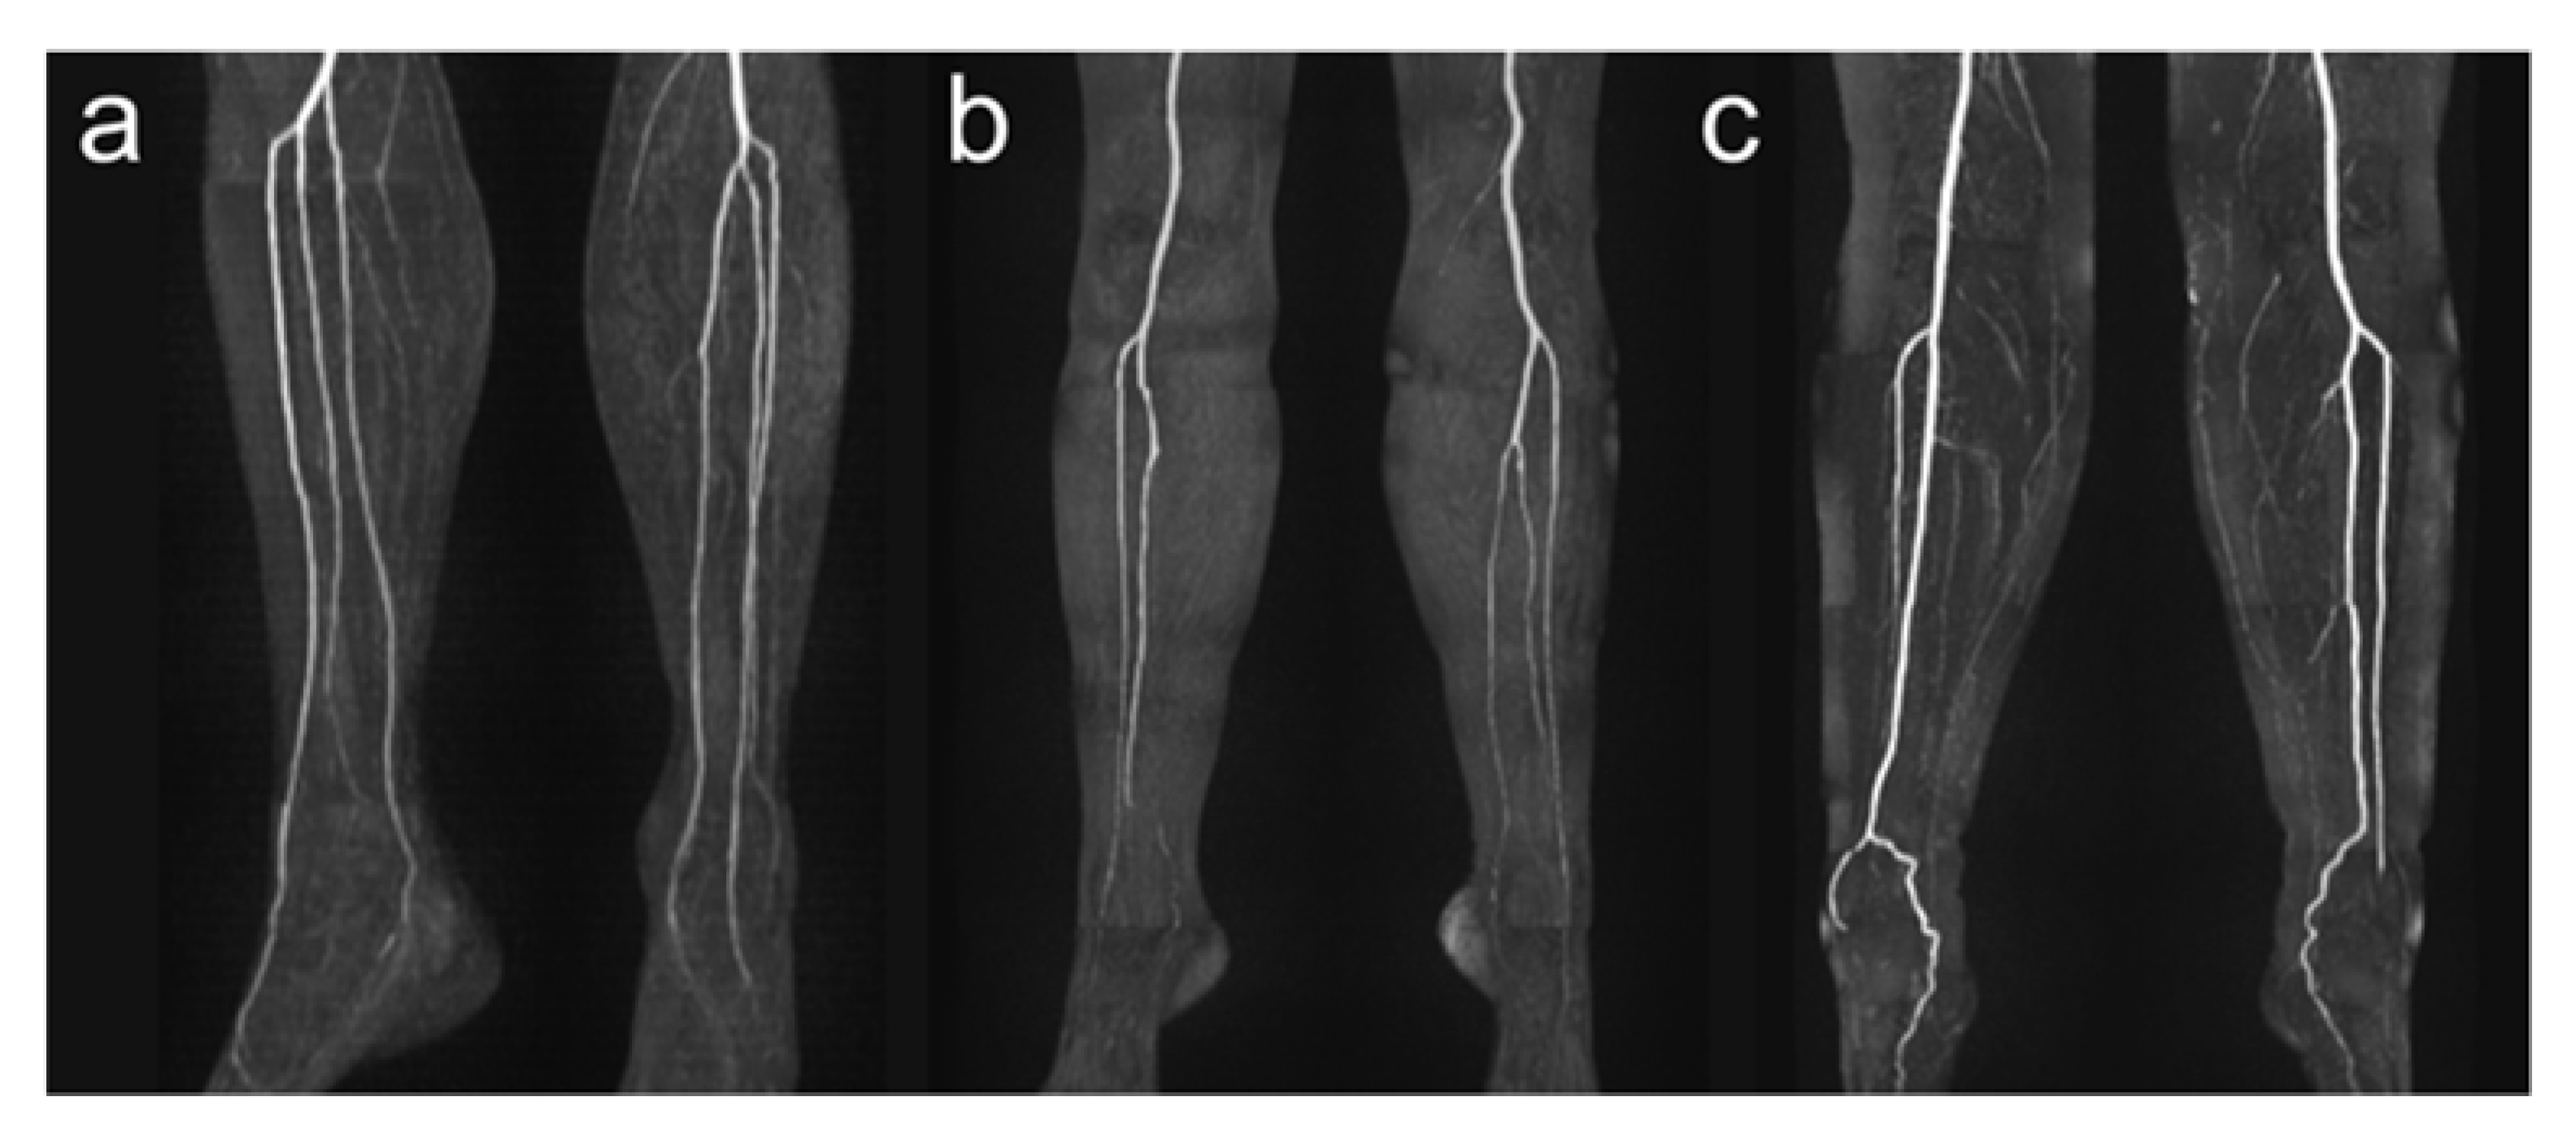

Detailed anatomic analysis of QISS-MRA source data of 100 legs according to the branching classification described by Kim et al. [19] revealed that in 87 cases (87.0%) a regular three-vessel supply was present (84.0% (42/50) in right legs and 90.0% (45/50) in left legs), in 5 cases (5.0%), a two-vessel supply (4.0% (2/50) in right legs, 6.0% (3/50) in left legs), and in no cases, a one-vessel supply. In eight legs, an irregular three-vessel supply was observed that was classified as type IC (two legs) or IIB (six legs). Four of five two-vessel supplies had a hypoplastic PT, and one leg a hypoplastic AT. Types I-B, II-A, II-C, and III-C were not identified in our patient population. Examples of anatomical vessel variations are demonstrated in Figure 3.

Figure 3.

Exemplary illustration of anatomical vessel variations of lower leg arteries. Panel (a) shows a type I-C according to Kim et al. [19] with the first exit of the PT below the knee joint with the subsequent exit of FA and AT via a common trunk. Panel (b) shows a hypoplastic PT (Type III-A) on the right side, and panel (c) shows a hypoplastic PT on both sides. Note the supply to the foot in these cases from the FA.